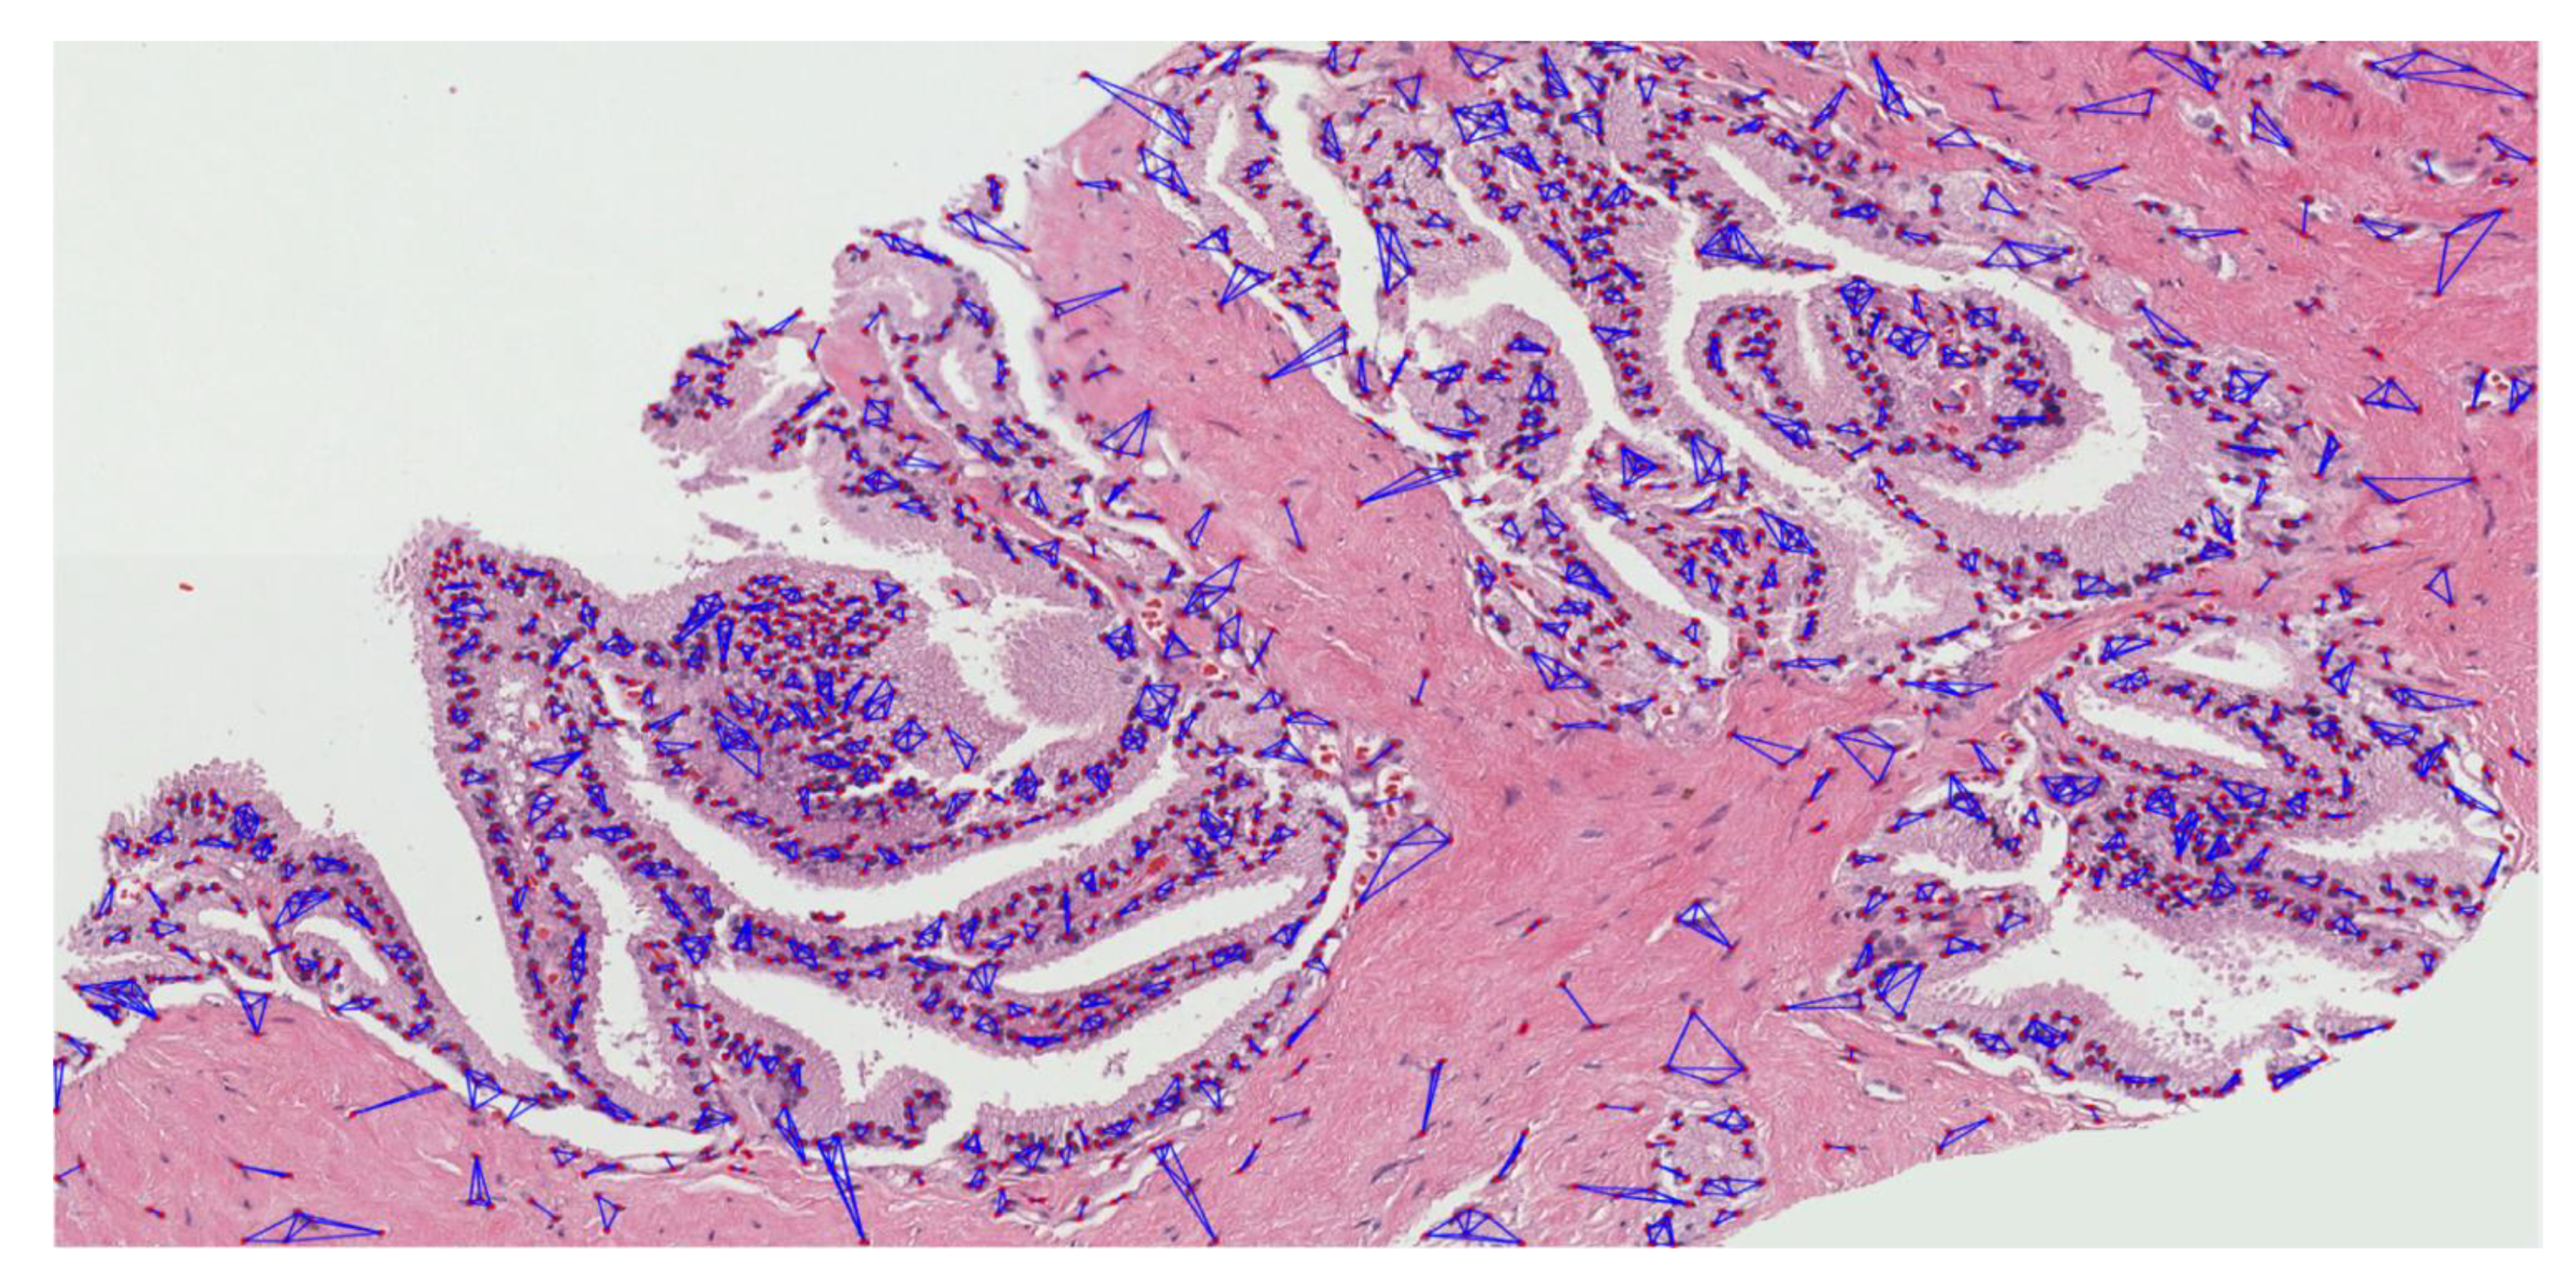

The MST cluster analysis method was applied on the PCa tissue samples of dataset 1 and dataset 2, and the visualization results of intra- and inter-cluster MST are shown in Figure 12. From the following figure, we can analyze that the structure and shape of the clusters in each grade are different from each other. It is quite challenging for researchers and doctors to analyze the microscopic biopsy images of PCa and identify suitable biomarkers compared to other common cancers.

Figure 12.

The visualization of intra- and inter-cluster MST graphs. (a–c) The intra-cluster MST of grade 3, grade 4, and grade 5, respectively. (d–f) The inter-cluster MST was generated from a, b, and c, respectively. The dotted red circle indicates the cluster of cell nuclei. Different color lines in a-c and d-f indicate intra- and inter-clusters, respectively.

The gold standard for the diagnosis of prostate cancer is a pathologist’s evaluation of prostate tissue. To potentially assist pathologists, DL-based cancer detection systems have been developed. Many of the state-of-the-art models are patch-based convolutional neural networks. Patch-based systems typically require detailed, pixel-level annotations for effective training. However, such annotations are seldom readily available in contrast to the clinical reports of pathologists, which contain slide-level labels. Our study sliced annotated and graded images from the pathologist, and we use an MST algorithm to perform cluster analysis and extract significant information for AI classification. The proliferation and cluster structure of cell nuclei, as shown in Appendix A, Figure A4 (Gleason pattern 3), Figure A5 (Gleason pattern 4), and Figure A6 (Gleason pattern 5), will help the pathologist to identify, classify, and grade more precisely the Gleason score assignment in the light of heterogeneity and variability.

The pathology annotated WSIs used in this research to analyze the pattern and community structure of cell nuclei in grades 3, 4, and 5, shown in Figure A1, Figure A2 and Figure A3, respectively. The cluster analysis was performed successfully on histological images of PCa. For visualization of the community structure of cell nuclei, we plot the clusters in the annotated regions of grade 3, grade 4, and grade 5 in WSIs, shown in Figure A4, Figure A5 and Figure A6, respectively.